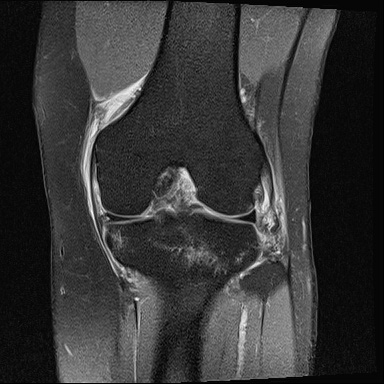

십자인대 파열 수술

십자인대가 완전 파열된 경우 기존의 인대를 제거하고,

환자의 상태에 따라 자가 인대/타가 인대를 이용해

새로운 인대를 연결해주는 관절내시경 수술이 시행됩니다.

ㆍ2014.11.03 관절내시경 당일 치료 전, 후 사진입니다.

수술전

2023.01.10

수술후

2023.01.18